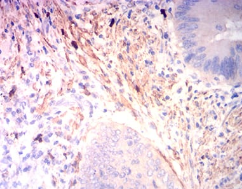

IHC    1/200 - 1/1000